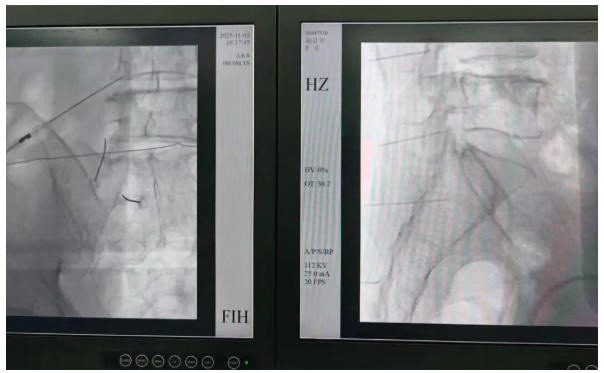

在X线或CT影像实时引导下,医生会将细如针尖的射频穿刺针精准送达患者病变椎间盘或受压迫神经根附近。接着通过神经电生理测试,准确复现患者的疼痛感受,一步锁定“责任神经”。这一过程既是精准诊断,更为后续治疗奠定坚实基础,真正实现“查得准、治得对”。